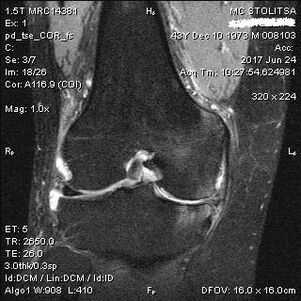

يتم تشخيص هشاشة العظام في مفصل الركبة في مكتب طبيب الروماتيزم أو جراح العظام. يقوم الطبيب بفحص المفصل المصاب، ويشعر به، ويستمع إلى الشكاوى ويطرح أسئلة إضافية. إجراء عدة اختبارات - على سبيل المثال، مطالبة المريض بثني ساقه أو اتخاذ بضع خطوات. إذا كان من الضروري بعد ذلك توضيح مرحلة المرض أو طبيعة التغيرات المرضية، فسوف يحولك لإجراء المزيد من الفحوصات. على سبيل المثال، التصوير المقطعي بالكمبيوتر أو التصوير الشعاعي.